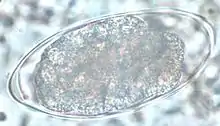

| Nippostrongylus brasiliensis | |